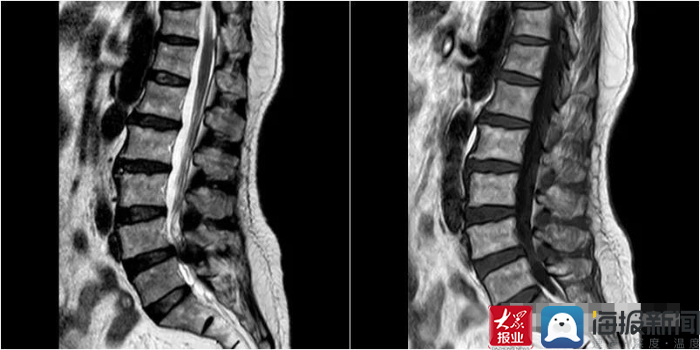

*安泰**市中医医院脊柱外科医师王乃舜对患者详细查体并完善相关检查后,发现患者多节段椎间盘突出,以腰4、5椎间盘为重,并相应黄韧带肥厚,腰4椎体滑脱,腰椎管严重狭窄,遂建议患者住院手术治疗。

考虑患者腰椎管狭窄严重,黏连较重,传统骨科器械操作时神经损伤风险极高,王乃舜决定采用一种新型的外科手术工具——超声骨刀为患者进行手术,术中以超声骨刀切断椎板、分离椎板及硬膜、分离粘连黄韧带。手术最终顺利完成,较之前传统手术方法极大的缩短了手术时间,减少术中出血,术后第二天患者即可以在支具辅助下自行下地行走,之前的症状也消失了。